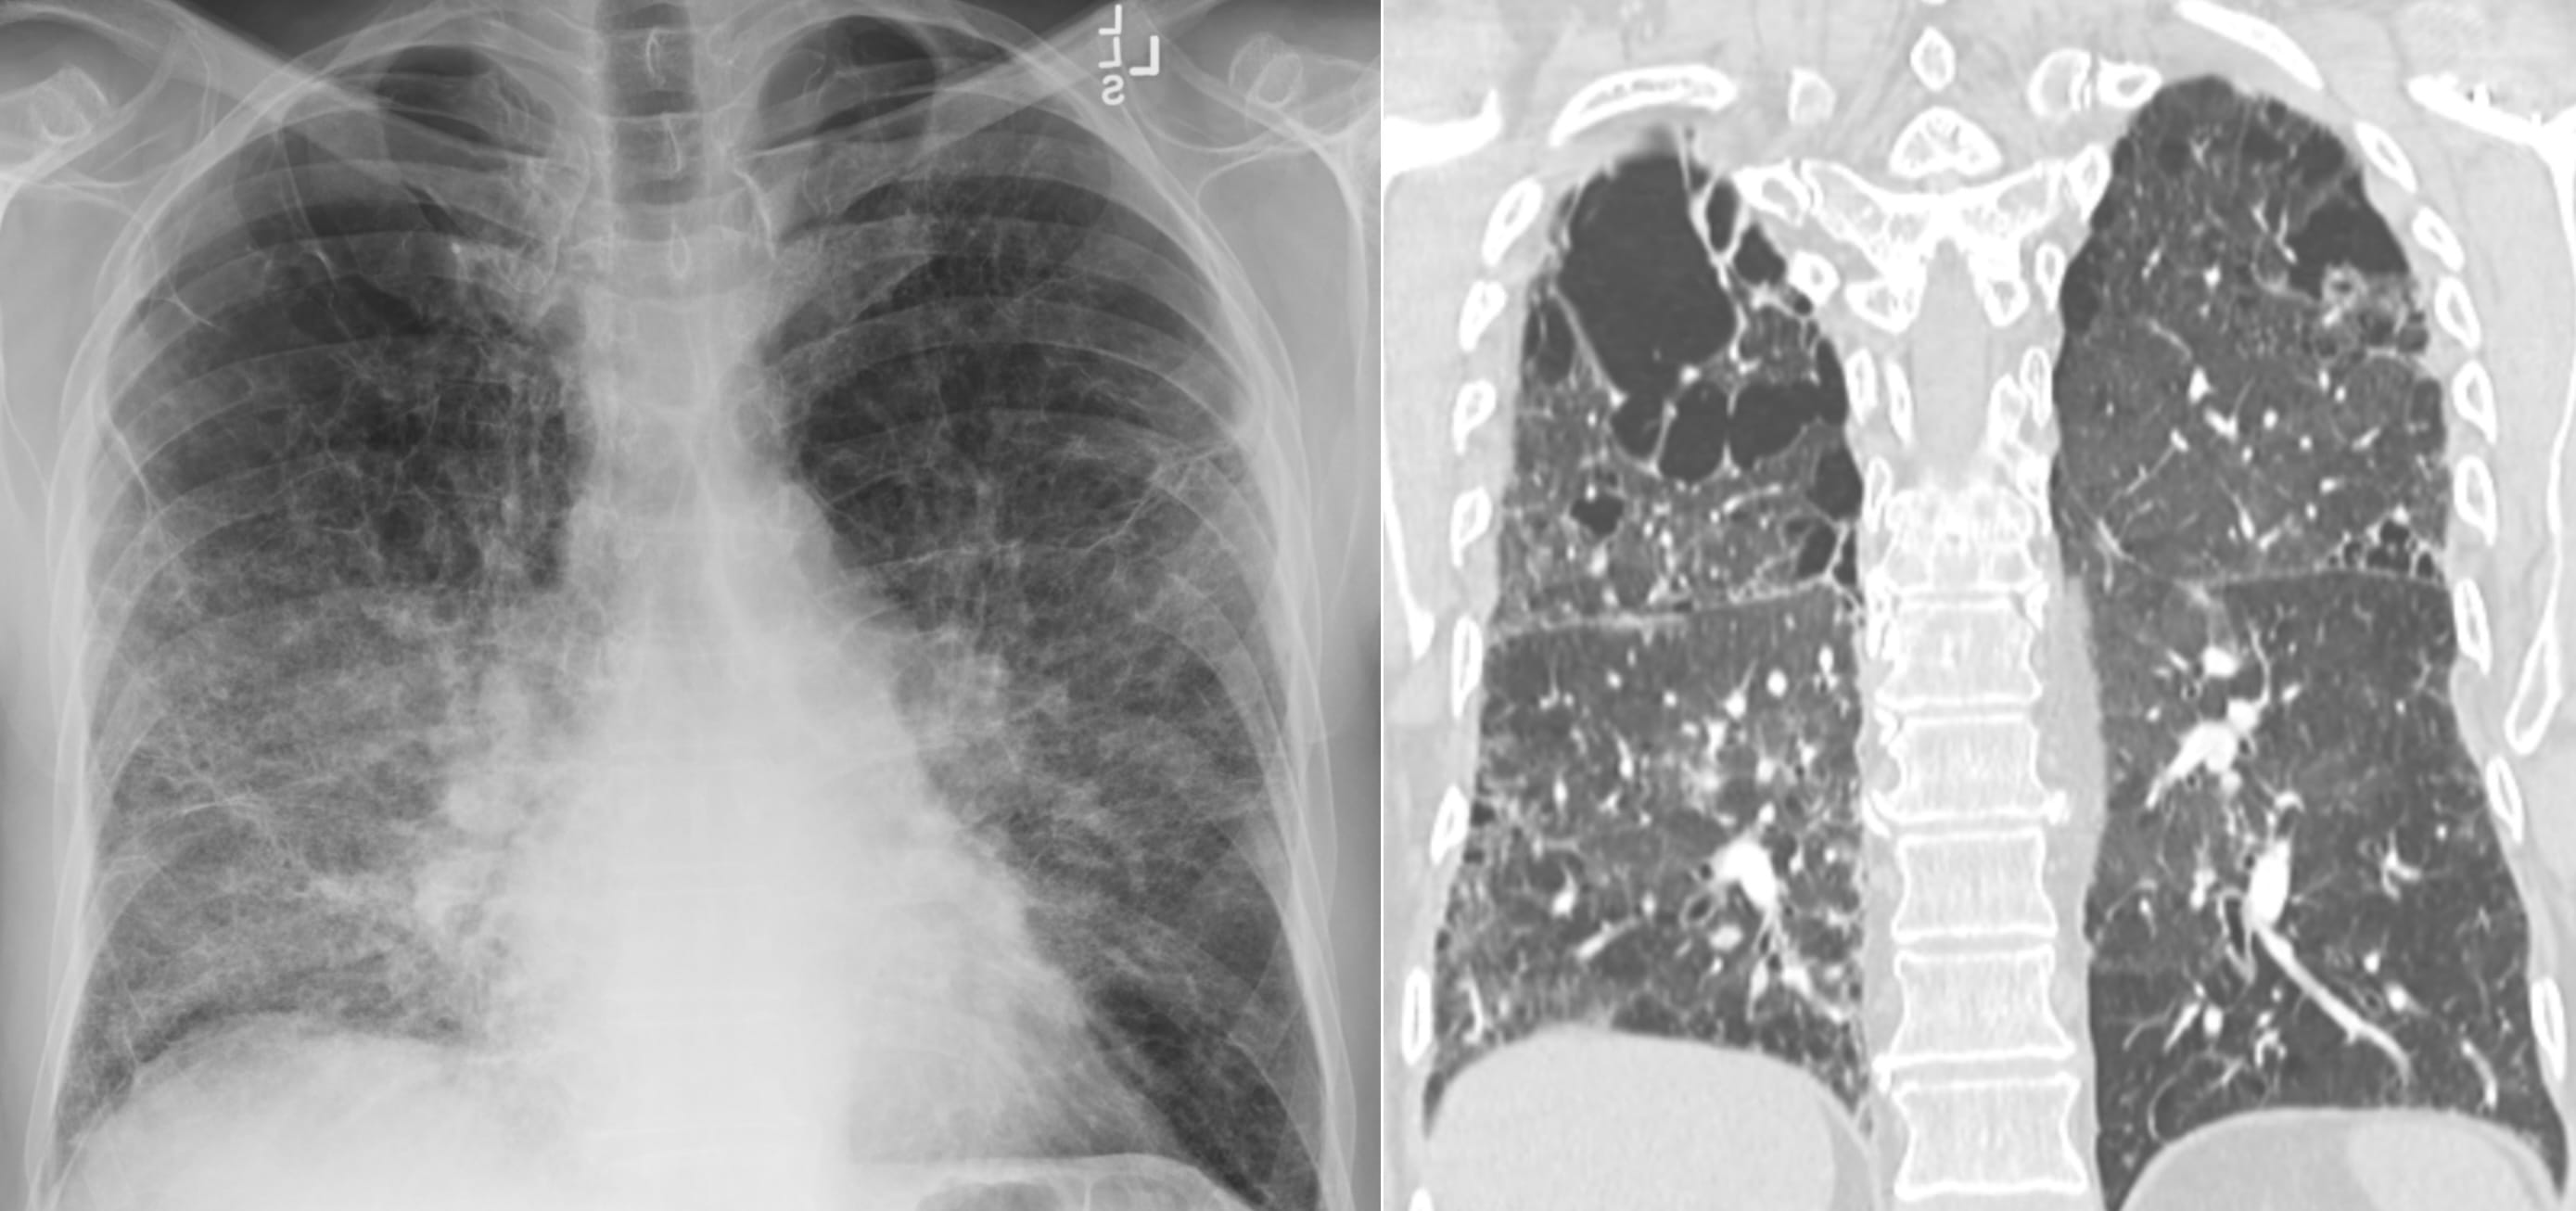

Suggested reporting terminology

“Findings of Smoker’s Lung are present in the form of: centrilobular emphysema in the upper lungs and patchy pulmonary ground glass opacities, consistent with accumulation of Smoker’s Macrophages and, possibly, Smoking-Related Interstitial Fibrosis.”

From the article:

“The cysts’ diameters in AEF are significantly larger than those in UIP and NSIP, but, at the same time, the walls are significantly thinner than those of UIP and thicker than those of centrilobular emphysema (CLE)”

Examples from the article:

One observation seems relevant: the cystic spaces may be situated away from the pleural surface.